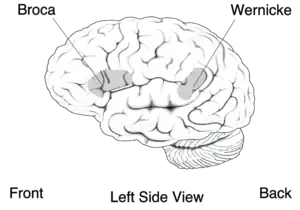

- Individuals with receptive aphasia (Wernicke's aphasia), also referred to as fluent aphasia, may speak in long sentences that have no meaning, add unnecessary words, and even create new "words" (neologisms). For example, someone with receptive aphasia may say, "delicious taco", meaning "The dog needs to go out so I will take him for a walk". They have poor auditory and reading comprehension, and fluent, but nonsensical, oral and written expression. Individuals with receptive aphasia usually have great difficulty understanding the speech of both themselves and others and are, therefore, often unaware of their mistakes. Receptive language deficits usually arise from lesions in the posterior portion of the left hemisphere at or near Wernicke's area.[9][63]: 71 It is often the result of trauma to the temporal region of the brain, specifically damage to Wernicke's area.[64] Trauma can be the result from an array of problems, however it is most commonly seen as a result of stroke[65]

- Individuals with expressive aphasia (Broca's aphasia) frequently speak short, meaningful phrases that are produced with great effort. It is thus characterized as a nonfluent aphasia. Affected people often omit small words such as "is", "and", and "the". For example, a person with expressive aphasia may say, "walk dog", which could mean "I will take the dog for a walk", "you take the dog for a walk" or even "the dog walked out of the yard." Individuals with expressive aphasia are able to understand the speech of others to varying degrees. Because of this, they are often aware of their difficulties and can become easily frustrated by their speaking problems.[66] While Broca's aphasia may appear to be solely an issue with language production, evidence suggests that it may be rooted in an inability to process syntactical information.[67] Individuals with expressive aphasia may have a speech automatism (also called recurring or recurrent utterance). These speech automatisms can be repeated lexical speech automatisms; e.g., modalisations ('I can't..., I can't...'), expletives/swearwords, numbers ('one two, one two') or non-lexical utterances made up of repeated, legal but meaningless, consonant-vowel syllables (e.g.., /tan tan/, /bi bi/). In severe cases, the individual may be able to utter only the same speech automatism each time they attempt speech.[68]

- Individuals with conduction aphasia have deficits in the connections between the speech-comprehension and speech-production areas. This might be caused by damage to the arcuate fasciculus, the structure that transmits information between Wernicke's area and Broca's area. Similar symptoms, however, can be present after damage to the insula or to the auditory cortex. Auditory comprehension is near normal, and oral expression is fluent with occasional paraphasic errors. Paraphasic errors include phonemic/literal or semantic/verbal. Repetition ability is poor. Conduction and transcortical aphasias are caused by damage to the white matter tracts. These aphasias spare the cortex of the language centers but instead create a disconnection between them. Conduction aphasia is caused by damage to the arcuate fasciculus. The arcuate fasciculus is a white matter tract that connects Broca's and Wernicke's areas. People with conduction aphasia typically have good language comprehension, but poor speech repetition and mild difficulty with word retrieval and speech production. People with conduction aphasia are typically aware of their errors.[66] Two forms of conduction aphasia have been described: reproduction conduction aphasia (repetition of a single relatively unfamiliar multisyllabic word) and repetition conduction aphasia (repetition of unconnected short familiar words.[73]

Localizationist approaches aim to classify the aphasias according to their major presenting characteristics and the regions of the brain that most probably gave rise to them.[75][76] Inspired by the early work of nineteenth-century neurologists Paul Broca and Carl Wernicke, these approaches identify two major subtypes of aphasia and several more minor subtypes:

- Expressive aphasia (also known as "motor aphasia" or "Broca's aphasia"), which is characterized by halted, fragmented, effortful speech, but well-preserved comprehension relative to expression. Damage is typically in the anterior portion of the left hemisphere,[77] most notably Broca's area. Individuals with Broca's aphasia often have right-sided weakness or paralysis of the arm and leg, because the left frontal lobe is also important for body movement, particularly on the right side.

- Receptive aphasia (also known as "sensory aphasia" or "Wernicke's aphasia"), which is characterized by fluent speech, but marked difficulties understanding words and sentences. Although fluent, the speech may lack in key substantive words (nouns, verbs, adjectives), and may contain incorrect words or even nonsense words. This subtype has been associated with damage to the posterior left temporal cortex, most notably Wernicke's area. These individuals usually have no body weakness, because their brain injury is not near the parts of the brain that control movement.

- Conduction aphasia, where speech remains fluent, and comprehension is preserved, but the person may have disproportionate difficulty repeating words or sentences. Damage typically involves the arcuate fasciculus and the left parietal region.[77]